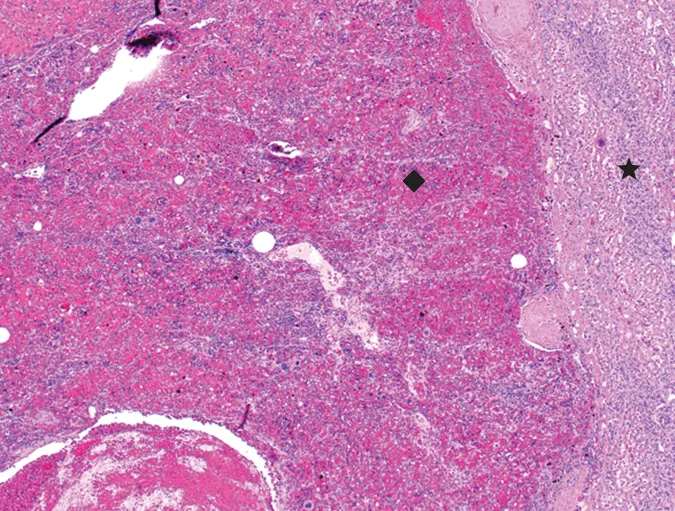

Although neoplasia was suspected, it could not be confirmed without histopathology. The owners elected for abdominal exploratory surgery to attempt either complete mass resection or debulking with biopsy for histopathology. The owners were prepared to consult with the oncology team following surgery if neoplasia was confirmed. Three liver masses and one mass adhered to the linea alba with omental adhesions were removed, leaving smaller masses and irregularities throughout the liver. The largest mass (11 cm), located in the left medial liver lobe, was firm and vascular and interspersed with pockets of unclotted blood. The left medial liver lobe containing the largest liver mass, 2 additional liver masses, and a mass adhered to the linea alba with omental adhesions were all removed, leaving smaller masses and irregularities throughout the liver. On histopathologic examination, the hepatic masses were found to be composed of red pulp, extramedullary hematopoietic tissue, rare white pulp, and smooth muscle trabeculae (Figure 3). The mass associated with the linea alba was also composed of ectopic splenic tissue, with similar components, consistent with splenosis. No evidence of neoplasia was seen. Recovery was uneventful, and the patient was discharged 2 days postoperatively.

Histopathology of hepatic mass with compressed hepatocytes (star) and splenic red pulp (diamond). Necrosis can be seen in the lower left corner.